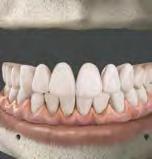

Férula de Descarga Digital de Nylon

La primera Férula de Descarga para tratar a pacientes con bruxismo y problemas de la ATM utilizando la tecnología más avanzada en impresión 3D.

Tecnología CAD/CAM para una óptima precisión y adaptación de la férula

Fabricada en Poliamida 12 con certificado en biocompatibilidad Clase IIa

Ligera, cómoda y con una alta resistencia al desgaste y a las fuerzas de la boca